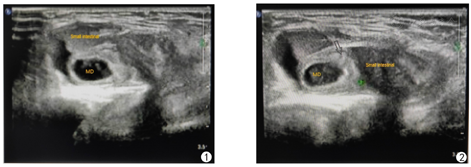

患儿,男,8岁,以"左侧腹股沟区不可复性肿物1 d余"为代主诉入院。1 d前家属发现患儿左侧腹股沟区出现一肿物,固定不能还纳,伴呕吐8次,非喷射性,为胃内容物,量较多,并伴腹痛、腹胀,无畏寒、发热,无腹泻、便秘,就诊于当地医院,考虑小肠梗阻,予以开塞露灌肠及输液等对症治疗,具体用药不详,症状无明显缓解,遂急诊转入院。入院后查体:患儿一般情况可,心、肺查体未见明显异常;腹膨隆,全腹轻压痛,无反跳痛;男性外阴;左侧腹股沟区触及一肿物,大小约3.5 cm×2.5 cm×2.5 cm,边界清,表面光滑,呈椭圆形,质韧,伴触痛,未坠入阴囊。用手将其向上进行挤压,不可还纳入腹腔,指压外环见外环口增宽。右侧腹股沟区未及肿物。双侧睾丸阴囊内未触及。血常规:白细胞计数(WBC)12.2×109/L,中性粒细胞百分率(NEUT) 49.3%。超声检查:①左侧腹股沟区可及一混合回声,大小约4.5 cm×1.8 cm×2.3 cm,边界清,其内为肠管回声,并可见一段异常肠袢,大小约2.5 cm×1.5 cm,壁增厚,回声减低,其一端与小肠相连,一端为盲端。此肿物向上延伸与腹腔相通,测疝径0.7 cm。见图1、图2。②双侧睾丸均位于腹股沟管,大小正常,轮廓规则,回声均匀。腹部DR平片:上腹部肠管胀气,并可见一长气液平面,中下腹部较密实,考虑肠梗阻。初步诊断为:1.左侧腹股沟嵌顿疝;2.不全性肠梗阻;3.双侧隐睾。遂于全身麻醉下行腹腔镜探查,术中见左侧腹股沟管内环口未闭,直径约0.8 cm,肠管位于内环口内,左侧睾丸位于左侧腹股沟管,可被牵拉入阴囊内,松手后睾丸回缩入腹股沟管内。右侧股沟股管内环口未闭,直径约0.5 cm,探查腹股沟管内环口远端约2.0 cm处可见睾丸回声,不能拉入阴囊内,向患儿家属告知病情后,暂不予以特殊处理。术中证实为左侧腹股沟嵌顿疝。腔镜直视下给予左侧腹股沟嵌顿疝复位,复位成功后见嵌顿肠管系膜对侧有一约1.5 cm×3.0 cm憩室,充血水肿,邻近肠管缺血坏死,长度约10.0 cm。首先于腔镜下常规行左侧疝囊高位结扎术,并沿脐窝下褶皱切口,用无损钳将憩室提出,处理回肠及憩室对应系膜,切除此段坏死肠管约10.0 cm及憩室,行端端吻合,全层间断缝合,浆肌层包埋,关闭系膜孔,逐层缝合切口。术后病理示:光镜下憩室内衬肠黏膜,肠壁及憩室淤血水肿、局部出血、少许炎细胞浸润(图3),考虑(回肠)Meckel憩室。术后患儿恢复良好,切口无明显疼痛,痊愈出院,术后1个月电话随访,状况良好,无特殊不适,疝无复发。